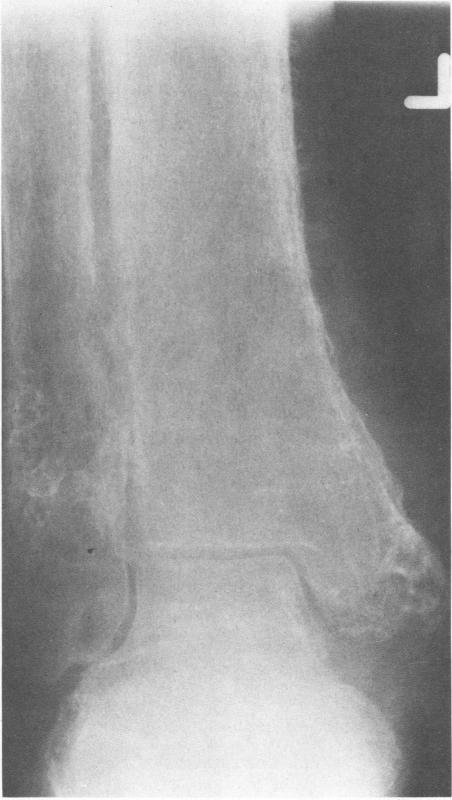

Herbert D A, Fessel W J

West J Med. 1981 Apr;134(4):354-7.